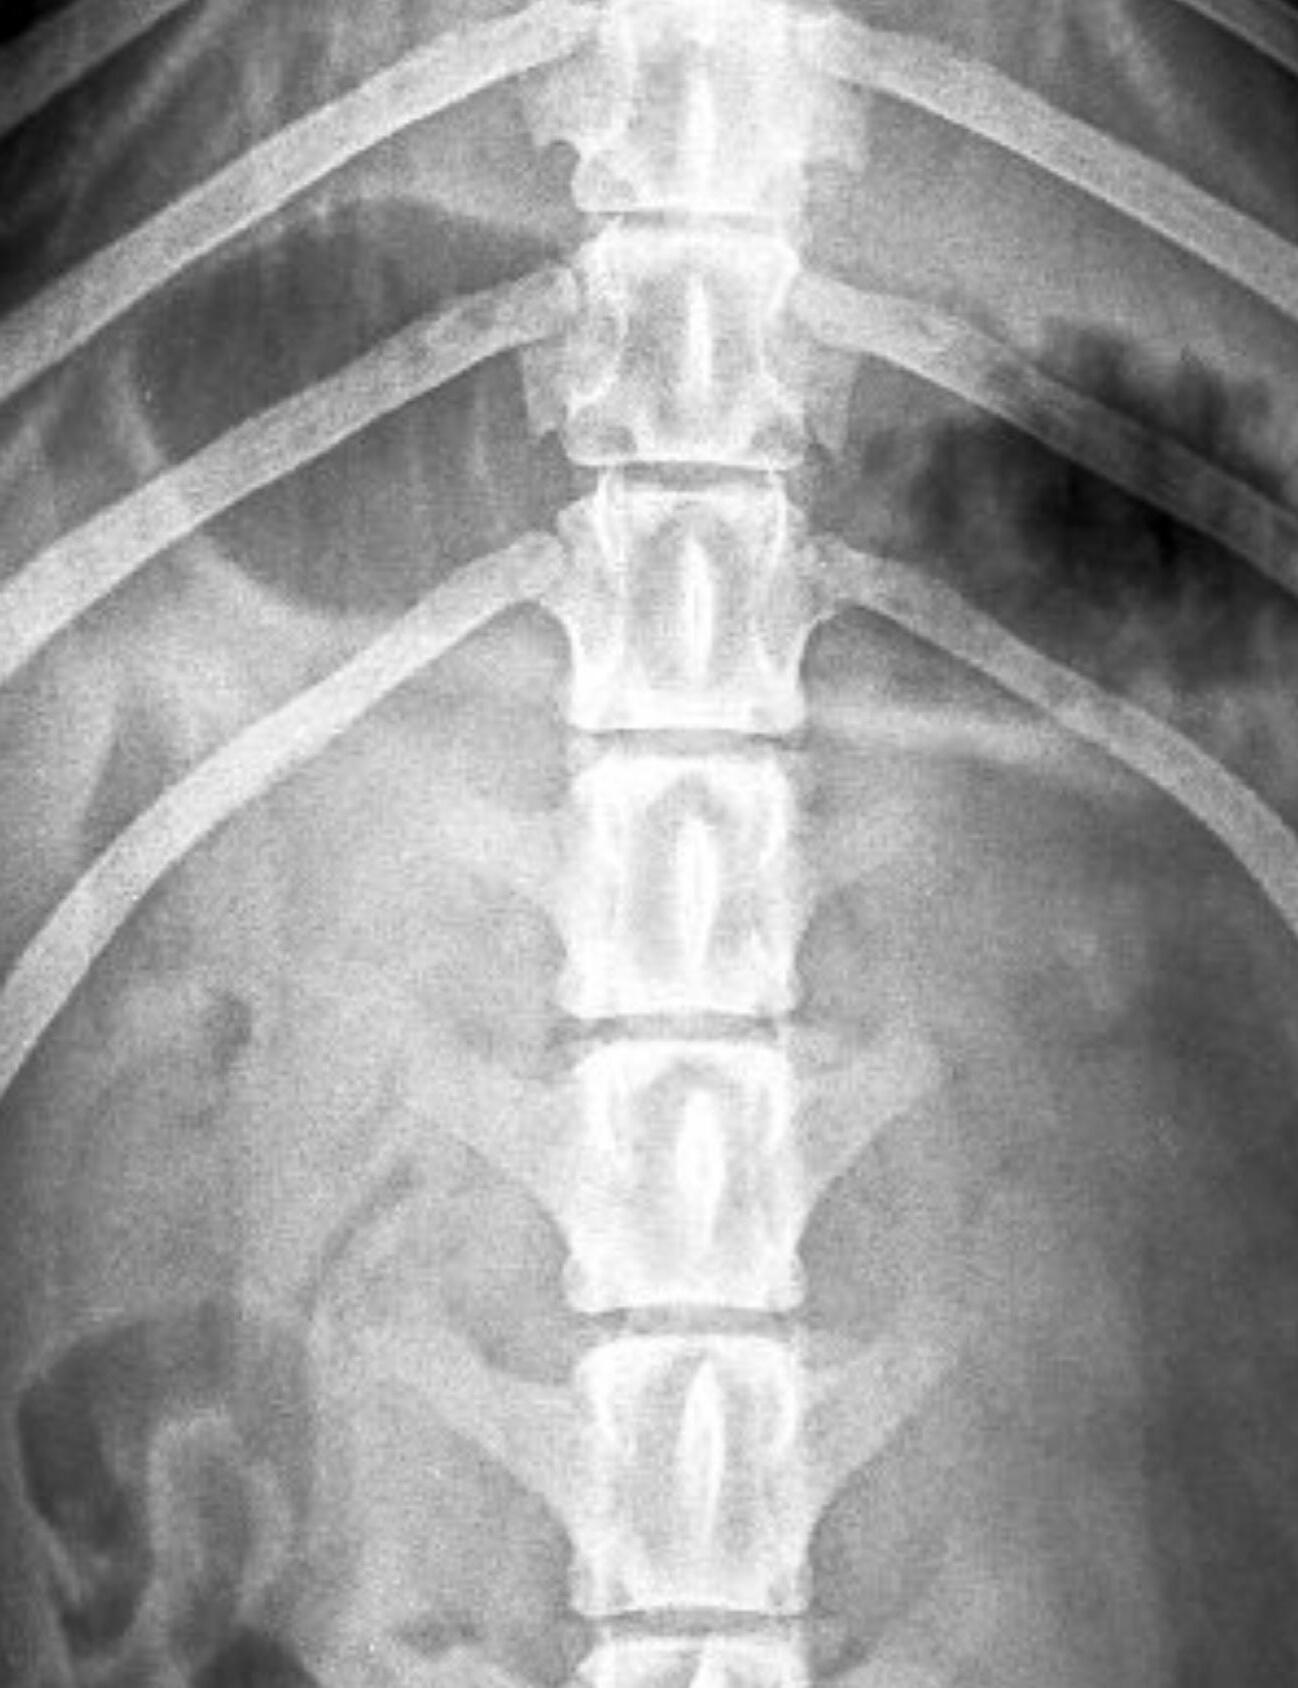

INTERVERTEBRAL DISC DISEASE (IVDD) AND REHABILITATION

In Part One we will be discussing Intervertebral Disc Disease, more commonly known as IVDD. IVDD is a condition of the spine that affects the intervertebral discs that are found between the vertebral bodies. In this condition, there is degeneration and herniation of these discs which puts pressure on the spinal cord which leads to pain and neurological symptoms. The condition mostly affects chondrodystrophic breeds, which are breeds who have short legs and long bodies such as Dachshunds, Pekingese, and Beagles. The condition commonly occurs in the mid to lower back, but can also occur in the neck. The condition can be painful and cause neurological deficits such as wobbliness, an inability to use their back legs, or complete paralysis of all four legs.

There are two types to this condition. The first is know as Type 1 or Hansen Type 1. This type happens suddenly and can be quite painful and goes along with significant neurological deficits. These are the little doggies who all of a sudden stop walking after jumping off a bed or couch, or after undergoing some form of impact. The second type is Type 2, or Hansen Type 2. This is a slow, degenerative condition with a gradual onset of symptoms. These companions often only have back pain, and later on there may be neurological symptoms. When the condition affects your companions neck, they may display symptoms such a pain when touching the neck, a low head carriage, stiffness when moving, vocalising when being touched, neck spasms, and in severe cases, front and hind limb paralysis.

Both types require veterinary attention, especially Type 1 which requires immediate veterinary attention. Your vet will assess your companion, make a diagnosis via means of x-rays, a CT scan, or an MRI, and discuss the way forward. Surgery is indicated for most, but this will be up to the vet and guardian.

Rehabilitation and physiotherapy are indicated for both surgical and nonsurgical management of IVDD. Before starting the physiotherapy journey, please get clearance from your vet or veterinary surgeon as to when they feel your companion will be ready. It is also advised to call your physiotherapist and get advice on when to make your first appointment as both routes will require cage rest before any form of outpatient therapy can begin.

Your physiotherapist will assess your companion and come up with a therapy program best suited to rehabilitating your companion. The goals of IVDD physiotherapy are centred around managing pain, preventing muscle atrophy when your companion is not able to walk, helping to restore coordination and proprioception (your companion’s ability to be aware of where their limbs are) and to manage any compensatoy issues your companion may be experiencing from overusing other parts of their bodies.

Rehabilitation programmes generally consist of:

• Massage to assist with pain and tense muscles

• Neuromuscular electrical stimulation to combat pain and build muscles

• Passive and active exercises to encourage weight bearing and prevent muscle atrophy, as well as teach your companion to walk again

• Acupuncture to assist with pain and nerve stimulation

• Ultrasound to assist with pain and healing

• Underwater treadmill or hydrotherapy to retrain your companion how to walk again, and to build muscles

• Hot and cold therapy to assist with healing and relax tense muscles

A lot of patience and perseverance is required when rehabilitating your companion after an IVDD incident. The rehabilitation can take weeks to months to years, and sometimes your companion unfortunately never regains the ability to walk again. There is a lot of home management and commitment required with these cases too. In saying that, there are many, many successful cases who recover fully. There is hope and a light at the end of the tunnel for most companions.